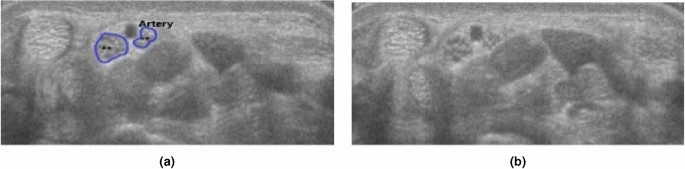

The ultrasound videos were manually segmented by an experienced rheumatologist using Annotation Web22 to delineate the median nerve by a polygon in 30–40 ultrasound images per participant. Each anatomical structure that was segmented, a different colour was assigned to (Fig. 1b). The epineurium (nerve sheath) of the median nerve was not included in the segmentation or outlining (Fig. 1). The images selected for segmentation were selected from all parts of the ultrasound scans, not only close to the wrist. Images were chosen according to their quality, so in areas with very blurry images segmentation was dropped, but in areas with good quality in the sense of distinguishability of the structures, images were segmented in close succession.

Bifid median nerve was found in three out of 51 wrists (5.8%), all healthy subjects. Persistent median artery was found in two cases (both together with a bifid median nerve, an example shown in Fig. 5).